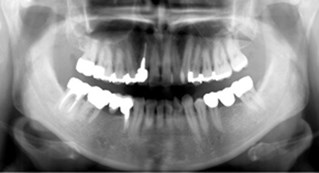

Helkäksröntgen (OPG)

I våra lokaler på Kungsgatan, finns det ett litet rum, "Silvia-rummet", som hyser vår digitala panoramaröntgen: OPG. Med denna röntgenapparat kan vi ta en bild av hela käken på en gång!

Du som patient står upp när bilden tas och du har ingen bildsensor inne i munnen, utan allt sker runt om käkens och huvudets utsida. Tidigare har vi varit tvungna att remittera våra patienter till en röngenspecialist för att få dessa bilder tagna. Panoramaröntgen behövs bl a inför implantatbehandlingar, vid käkskador, för bedömning av käkleder, men också vid förhandsprövningar till Försäkringskassan .

För att öka patientsäkerheten (att kunna hitta dolda tandinfektioner etc) kommer en sådan bild att tas på alla nya patienter vid första undersökningstillfället som en referensbild. Vi vill dessutom ta sådana bilder på samtliga patienter över 40 år som erhållit större fyllningar, genomgått rotbehandlingar - allt som ett led i att, på ett tidigt stadium, kunna upptäcka sjukdomsförändringar i både tänder, käkben och i angränsande vävnader.